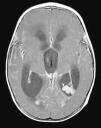

Radiología Solución del caso 30. Papiloma de los plexos coroideos con realce meníngeo

Solución del caso 30. Papiloma de los plexos coroideos con realce meníngeo

Solution to case 30. Choroid plexus papilloma with meningeal enhancement